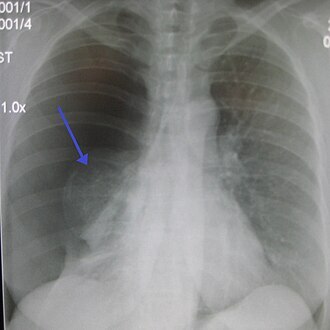

-Rx pulmonaire pour vérifier l’emplacement et la réexpansion du poumon